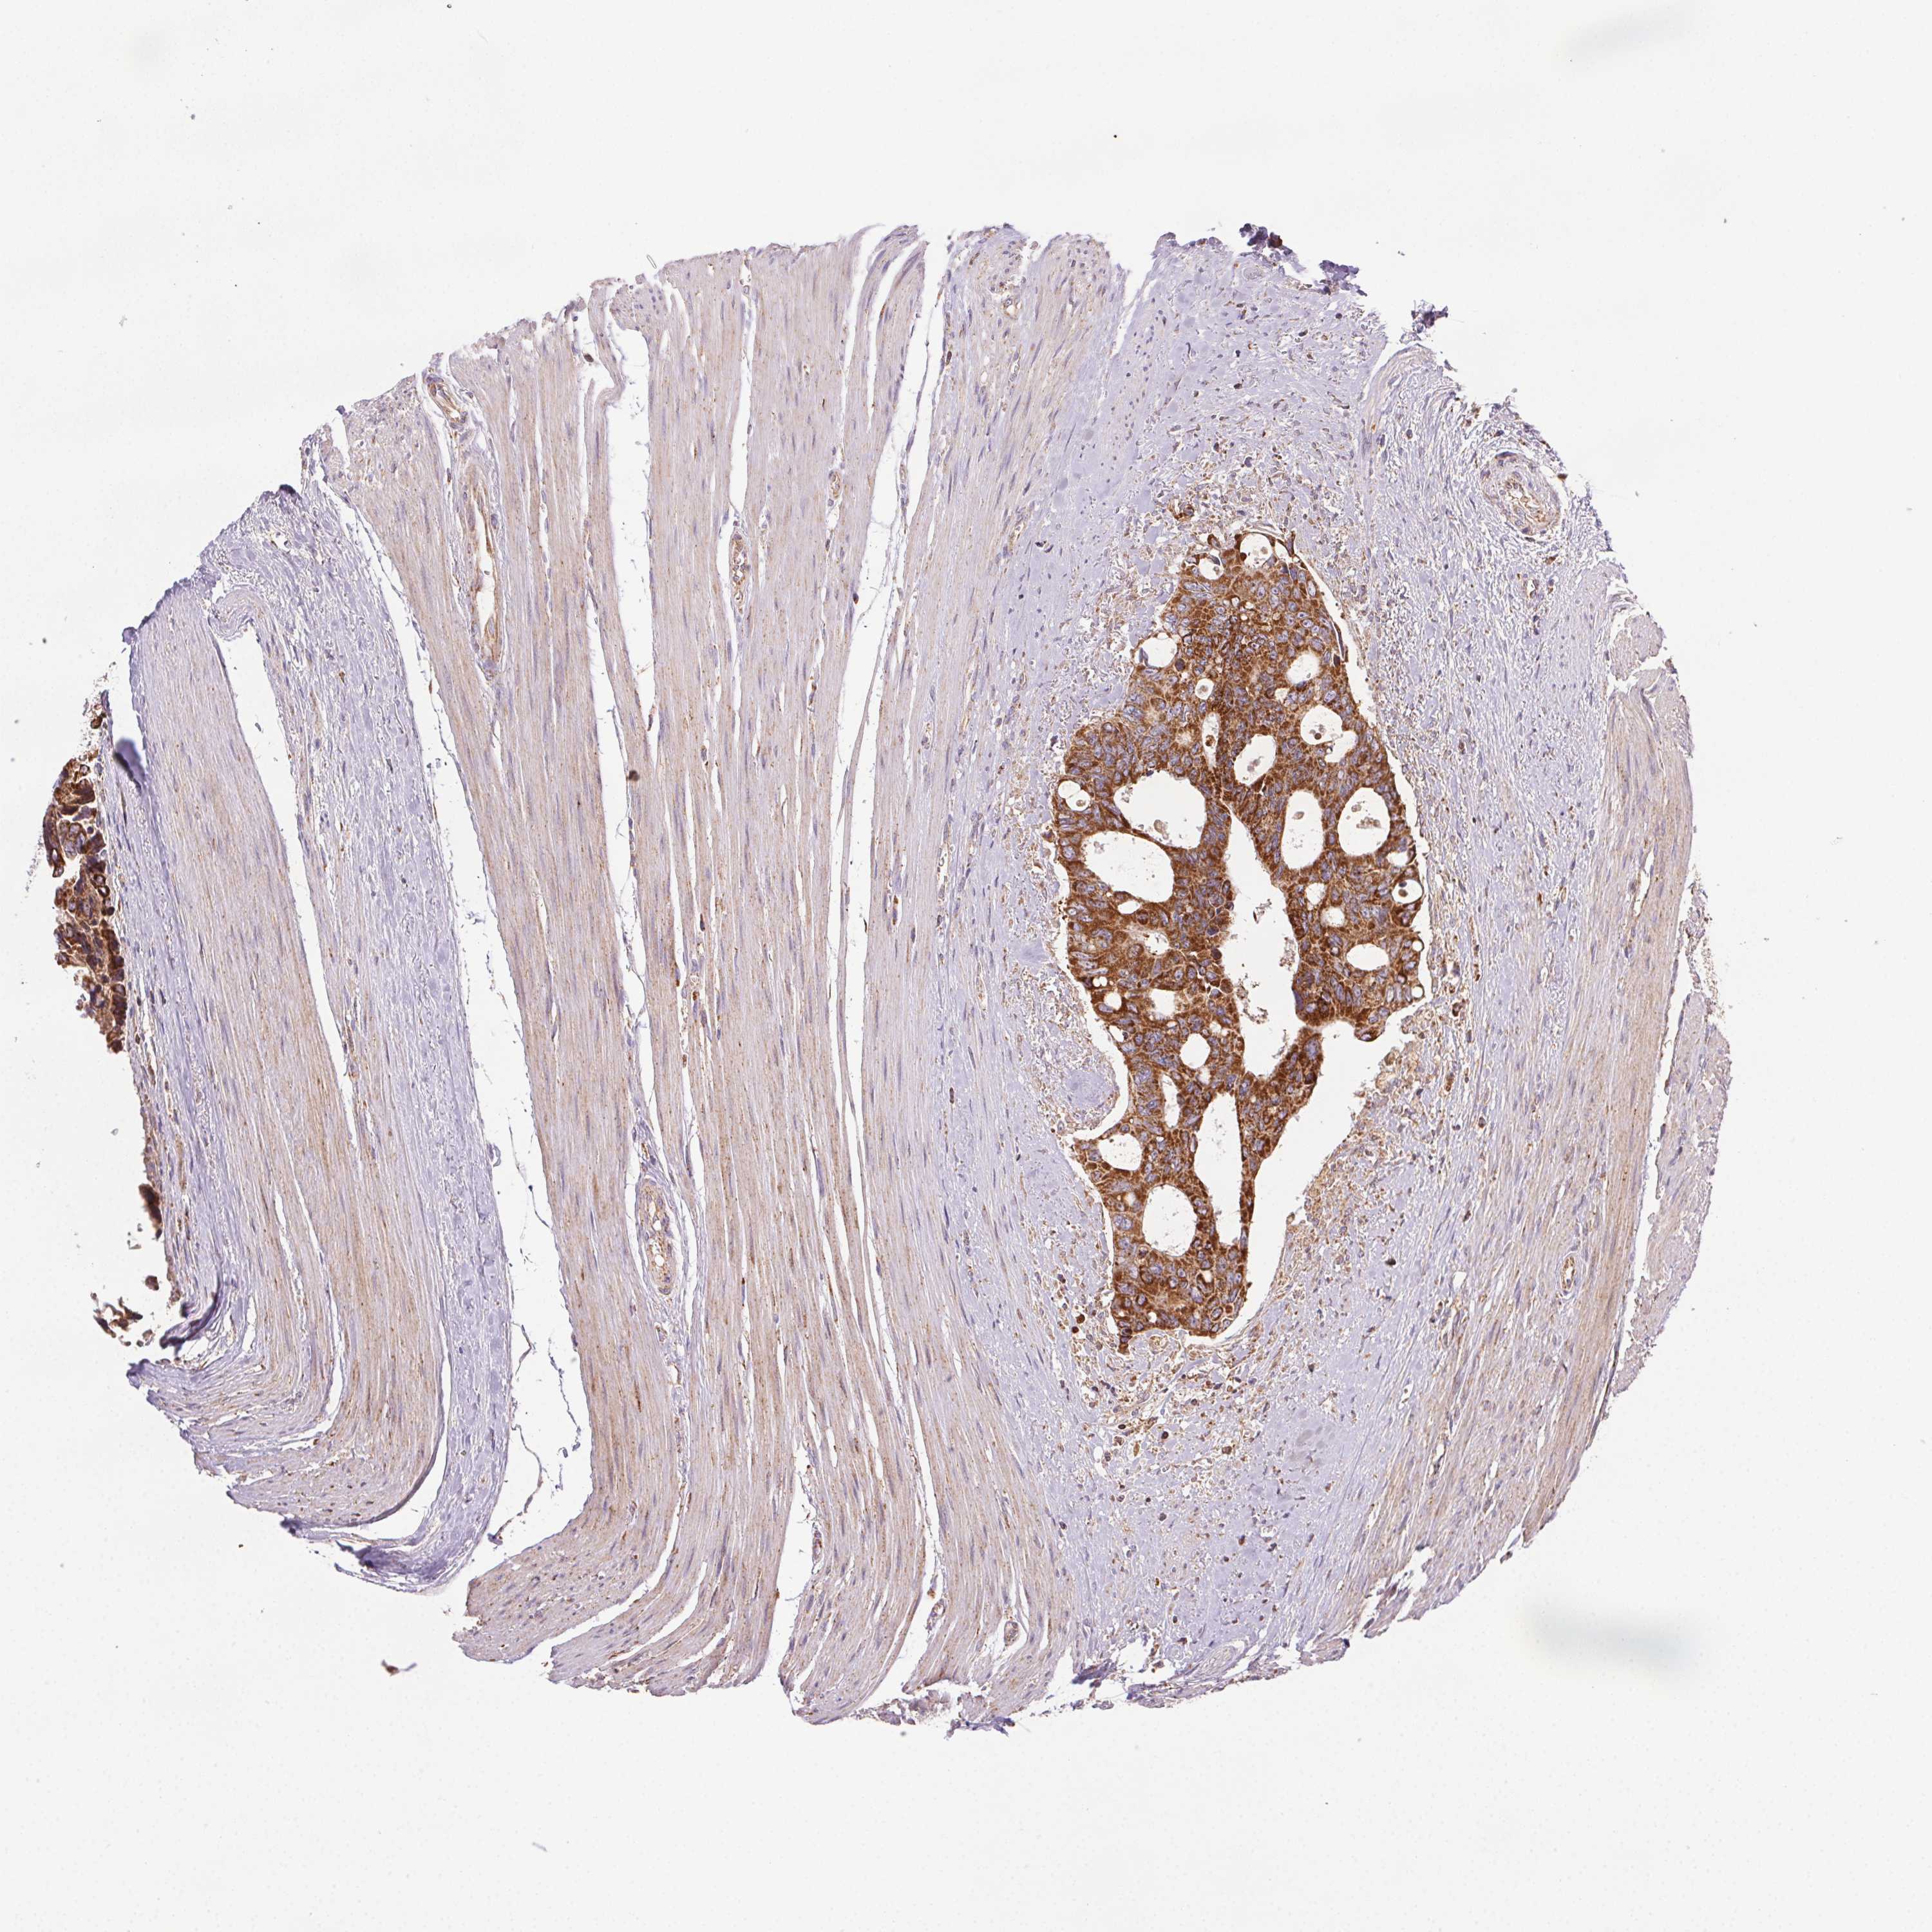

CANCER COLORECTAL CANCER Show tissue menu

Colorectal cancer

Human cancer

Colon adenocarcinoma

Rectum adenocarcinoma